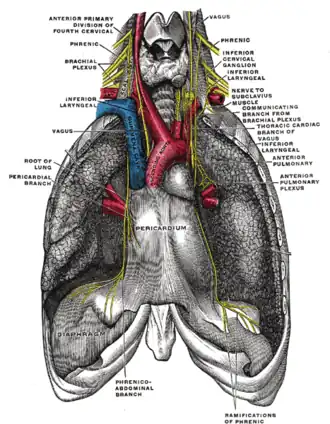

The phrenic nerve as it passes through the thorax to supply the diaphragm. | |

The phrenic nerve is a mixed nerve that originates from the C3–C5 spinal nerves in the neck. The nerve is important for breathing because it provides exclusive motor control of the diaphragm, the primary muscle of respiration. In humans, the right and left phrenic nerves are primarily supplied by the C4 spinal nerve, but there is also a contribution from the C3 and C5 spinal nerves. From its origin in the neck, the nerve travels downward into the chest to pass between the heart and lungs towards the diaphragm.

The phrenic nerve originates in the phrenic motor nucleus in the ventral horn of the cervical spinal cord. It descends obliquely with the internal jugular vein across the anterior scalene, deep to the prevertebral layer of deep cervical fascia and the transverse cervical and suprascapular arteries. On the left, the phrenic nerve crosses anterior to the first part of the subclavian artery. On the right, it lies on the anterior scalene muscle and crosses anterior to the 2nd part of the subclavian artery. On both sides, the phrenic nerve usually runs posterior to the subclavian vein as it enters the thorax where it runs anterior to the root of the lung and between the fibrous pericardium and mediastinal parietal pleura.[2]

- The right phrenic nerve passes over the brachiocephalic artery, posterior to the subclavian vein, and then crosses the root of the right lung anteriorly and then leaves the thorax by passing through the vena caval foramen opening in the diaphragm at the level of T8. The right phrenic nerve passes over the right atrium.

- The left phrenic nerve passes over the pericardium of the left ventricle and pierces the diaphragm separately.

The pericardiacophrenic arteries and veins travel with their respective phrenic nerves.

Both of these nerves supply motor fibers to the diaphragm and sensory fibers to the fibrous pericardium, mediastinal pleura, and diaphragmatic peritoneum.